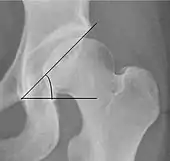

Tönnis angle | ![]() |

Slope of the sourcil (the sclerotic weight-bearing portion of the acetabulum) | 0 to 10°